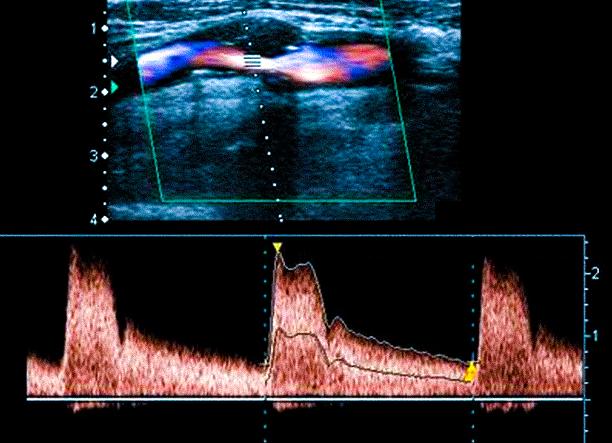

Дуплексное ангиосканирование

Так называется УЗИ сосудов ног, основанное на классической допплерографии. Исследование отличается лишь тем, что на мониторе врач видит картинку в цвете. Это дает возможность более точно оценить скорость и направление кровотока. Дуплексное сканирование кровеносных сосудов проходит по той же схеме, что и классическое, но результаты получаются более точными, исчерпывающими.

Дуплексное ангиосканирование, или УЗДС, отличается от первого наличием возможностей цветного картирования, позволяющего дополнительно определять направленность тока крови. Потоки, следующие в разных направлениях, приобретают различные цвета, что является для специалиста неоценимой информацией, дающей возможность комплексно определять показатели состояния сосудов.